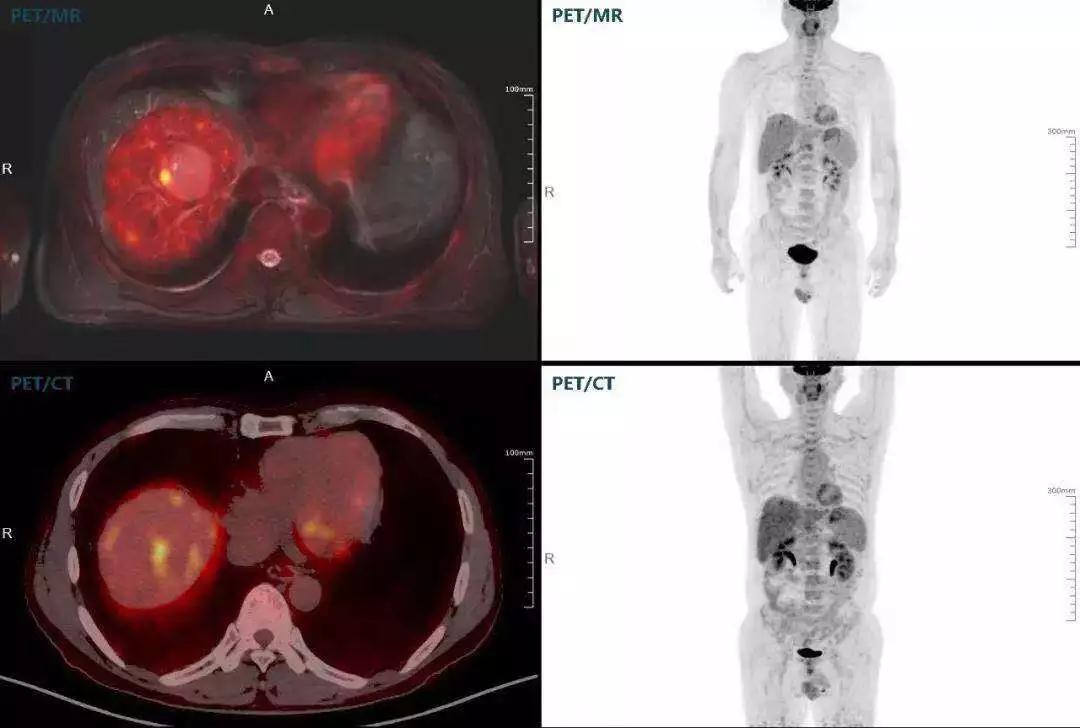

聯(lián)影“時空一體”超清TOF PET/MR搭載的壓縮感知技術(shù),能夠同時實現(xiàn)16期成像,精準(zhǔn)捕獲肝臟動態(tài)影像的每一瞬間,同時兼顧早期與晚期等全部期相的完整病灶信息,實時、全方位鎖定病灶。同時,基于其2.8mm超高分辨率,能夠精細(xì)呈現(xiàn)腫瘤邊界信息,捕捉局部微小病灶與遠(yuǎn)端轉(zhuǎn)移灶,助力醫(yī)生精準(zhǔn)診斷。

(對于同一例肝臟惡性腫瘤,PET-CT與PET/MR成像對比。可以看到,聯(lián)影PET/MR圖像對腫瘤邊界和FDG高濃聚區(qū)域清晰顯示。)